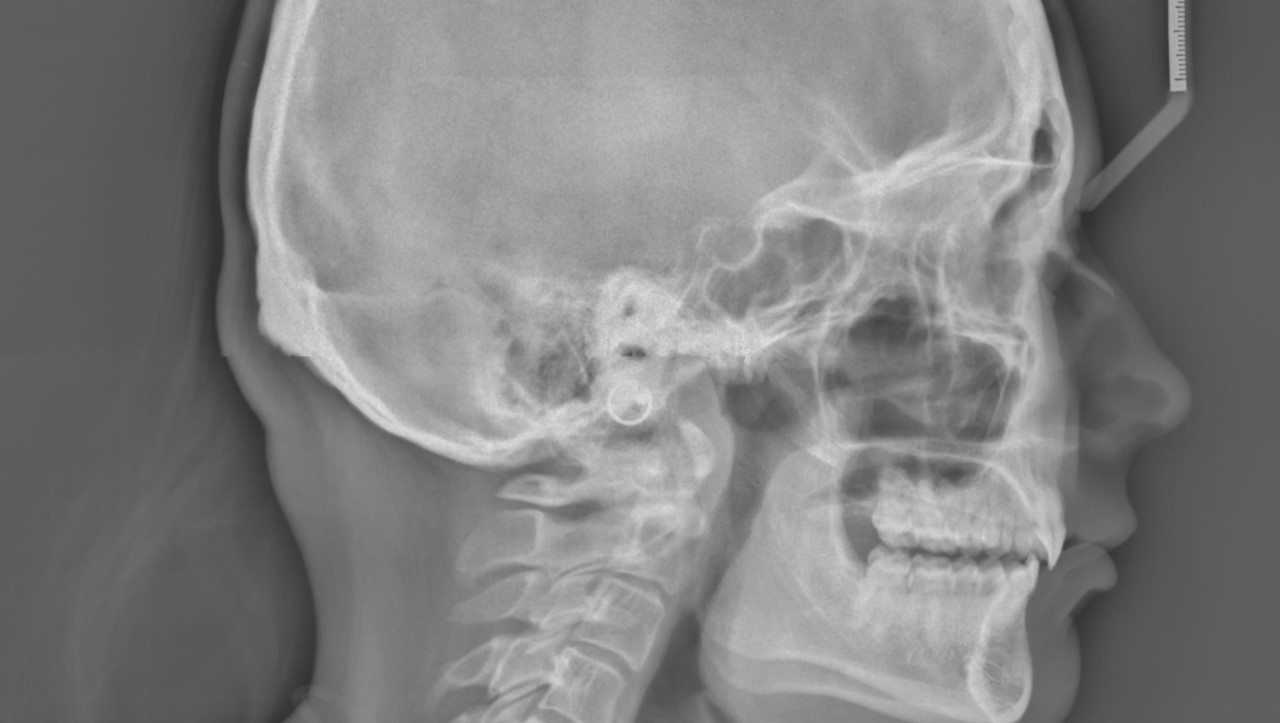

Corrective (Jaw) Surgery Mary E. Burns D.M.D. New Hope Pennsylvania Jaw Surgery Medically Necessary Why do i need a tmjr? jaw surgery is appropriate after growth stops, usually around ages 14 to 16 years for females and ages 17 to 21 years for males. jaw surgery may involve surgery to your upper jaw (maxilla) or the lower jaw (mandible) or a combination of both depending on your concerns and individual. jaw. Jaw Surgery Medically Necessary.

Corrective jaw surgery for micrognathia Alila Medical Images Jaw Surgery Medically Necessary jaw surgery is typically performed to help readjust or correct the alignment of your jaw. the jaw surgery is performed under general anaesthetic and you should expect to have one or two nights in hospital afterwards. jaw surgery may involve surgery to your upper jaw (maxilla) or the lower jaw (mandible) or a combination of both depending. Jaw Surgery Medically Necessary.